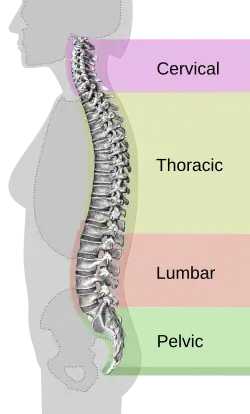

Wearing high-heeled shoes is strongly associated with injury, including injury requiring hospital care. There is evidence that high-heel-wearers fall more often, especially with heels higher than 2.5 cm,[7] even if they were not wearing high heels at the time of the fall.[6] Wearing high heels is also associated with musculoskeletal pain,[6] specifically pain in the paraspinal muscles (muscles running up the back along the spine)[1] and specifically with heel pain and plantar calluses (only women tested).[7]

A 2001 survey conducted by Pennsylvania State University of 200 women found that 58% of women complained of lower back pain when wearing heels, and 55% of women said they felt the worst overall back pain when wearing the highest heel.[29] The same study argues that as heel height increases, the body is forced to take on an increasingly unnatural posture to maintain its center of gravity. This changed position places more pressure and tension on the lower lumbar spine, which may explain why some of the women complained of severe back pain at a higher heel length.

In a 2016 study from Sahmyook University in Korea, researchers investigated the effects of high heels on the activation of muscles in the cervical and lumbar portions of the spine.[35] Thirteen women were recruited to walk down a walkway in three different testing conditions: barefoot, in 4 cm heels and in 10 cm heels. Surface electrodes were placed on the muscle mass of the women's spines and their feet to measure the electrical activity of muscles at different points of movement. The study results indicated an increase in both cervical and lumbar muscle activation as heel height increased: the cervical spine, the neck assists in maintaining head stability and postural control in the body. The usage of high heels shifts the body's center of mass, which requires the spine to adjust itself to maintain balance. The researchers mentioned that these results would increase local muscle fatigue over time, which could lead to muscle swelling, decreased muscle movement, and, in extreme cases of overuse, tissue deformation.